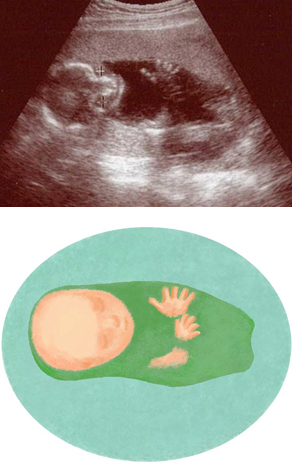

妊娠18週ころの超音波写真

関節がわかるほど骨格も成長してきました

頭のまわりの白い線は、頭蓋骨に当たります。指1本1本が、関節ごとにくっきり。赤ちゃんは普段手を握っていることが多いので、手の断面は丸く写ることが多いでしょう。